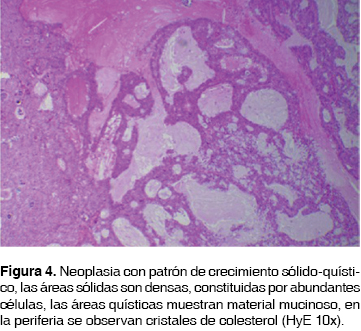

El reporte histopatológico de la resección quirúrgica mencionó carcinoma adenomatoideo quístico traqueal de 3.7 cm en su diámetro mayor con invasión perineural y linfovascular, bordes quirúrgicos sin tumor. Ganglios linfáticos con hiperplasia linfoide folicular y congestión sinusoidal (figura 4). Actualmente con 15 meses de seguimiento la paciente presenta buena evolución.